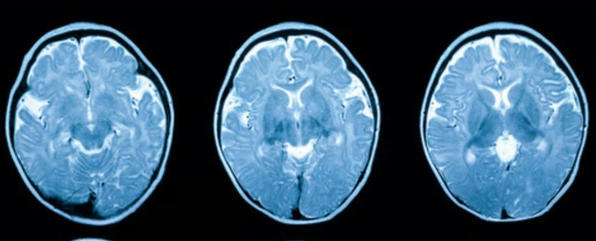

Supplements even with a Healthy Diet? Cancer Screening, Hydrating Food, Neurodegeneration, Lower Stroke Risk, Dietary Fiber, Is Larger Brain Healthier? and more...